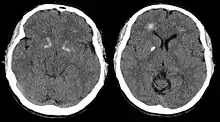

Brain computer tomography cuts of the person, demonstrating basal ganglia and periventricular calcification[44]